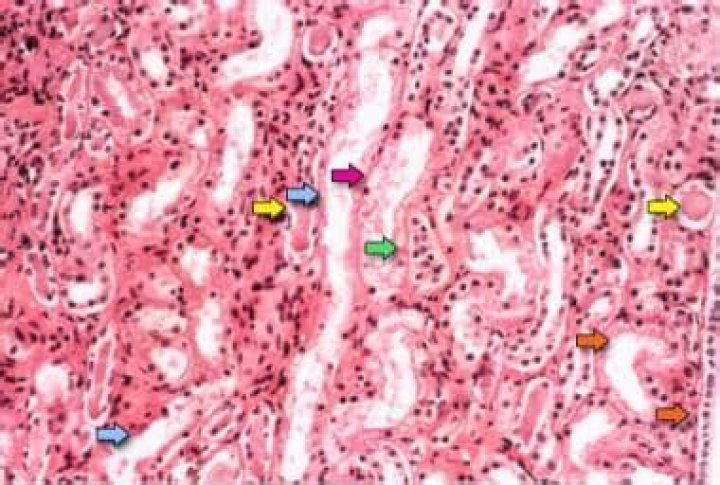

Acute tubular necrosis (ATN) is the most common cause of acute kidney injury (AKI) in the renal category (that is, AKI in which the pathology lies within the kidney itself). The term ATN is actually a misnomer, as there is minimal cell necrosis and the damage is not limited to tubules.

Acute tubular necrosis is kidney injury caused by damage to the kidney tubule cells (kidney cells that reabsorb fluid and minerals from urine as it forms). Common causes are low blood flow to the kidneys (such as caused by low blood pressure), drugs that damage the kidneys, and severe bodywide infections.

Acute tubular necrosis causes marked arteriolar vasoconstriction; the degree of vasoconstriction is related to the severity of the ATN. The Doppler hallmark of ATN is therefore reduced diastolic flow, reflected as an elevated resistance index (RI).